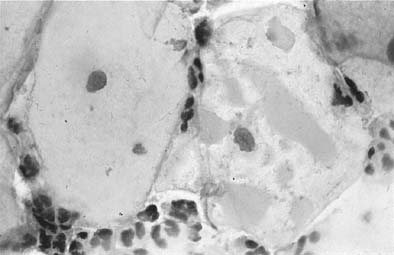

Changes caused by inflammation include metaplasia, surface reactions, such as hyperkeratosis and parakeratosis, and reparative processes.23 Frequently, the nuclei of the epithelial cells show enlargement, but the chromatin is fine, and cytoplasmic changes are variable (Fig. 1). In other instances, degenerative changes occur.23 The background may show numerous polymorphonuclear leukocytes and debris, a large number of bacterial forms, and histiocytes. When this exudate obscures the surface of the epithelial cells, it is advisable to treat the infection and repeat the smears because dysplastic or malignant cells may be hiding beneath the white blood cells, bacteria, and debris. Nonspecific vaginitis is commonly seen in patients harboring flora such as mixed bacteria or coccobacilli. Occasionally, cells show inflammatory changes in a background of rod bacteria that appear to be Döderlein’s bacilli. These bacteria belong to a heterogeneous group of organisms, and they morphologically resemble other microorganisms that may cause inflammatory changes in the epithelial cells. The presence of some polymorphonuclear leucocytes by itself is not an indication of inflammation, reactive changes in the epithelial cells are necessary.

Fig. 1. Clue cell showing slight enlargement of nuclei with dense cytoplasm covered by coccobacilli forms.(Papanicolaou, × 900).

Bacteria.

Gardnerella vaginalis, mobilincus, and other anaerobic bacteria (bacterial vaginosis) may be found in asymptomatic women (40% to 50% of patients), and other women may develop leukorrhea and an inflamed vaginal mucosa (see Fig. 1).23 Smears show cells covered by bacteria, so called clue cells, against a background of feathery cocobacillary forms (see Fig. 1).